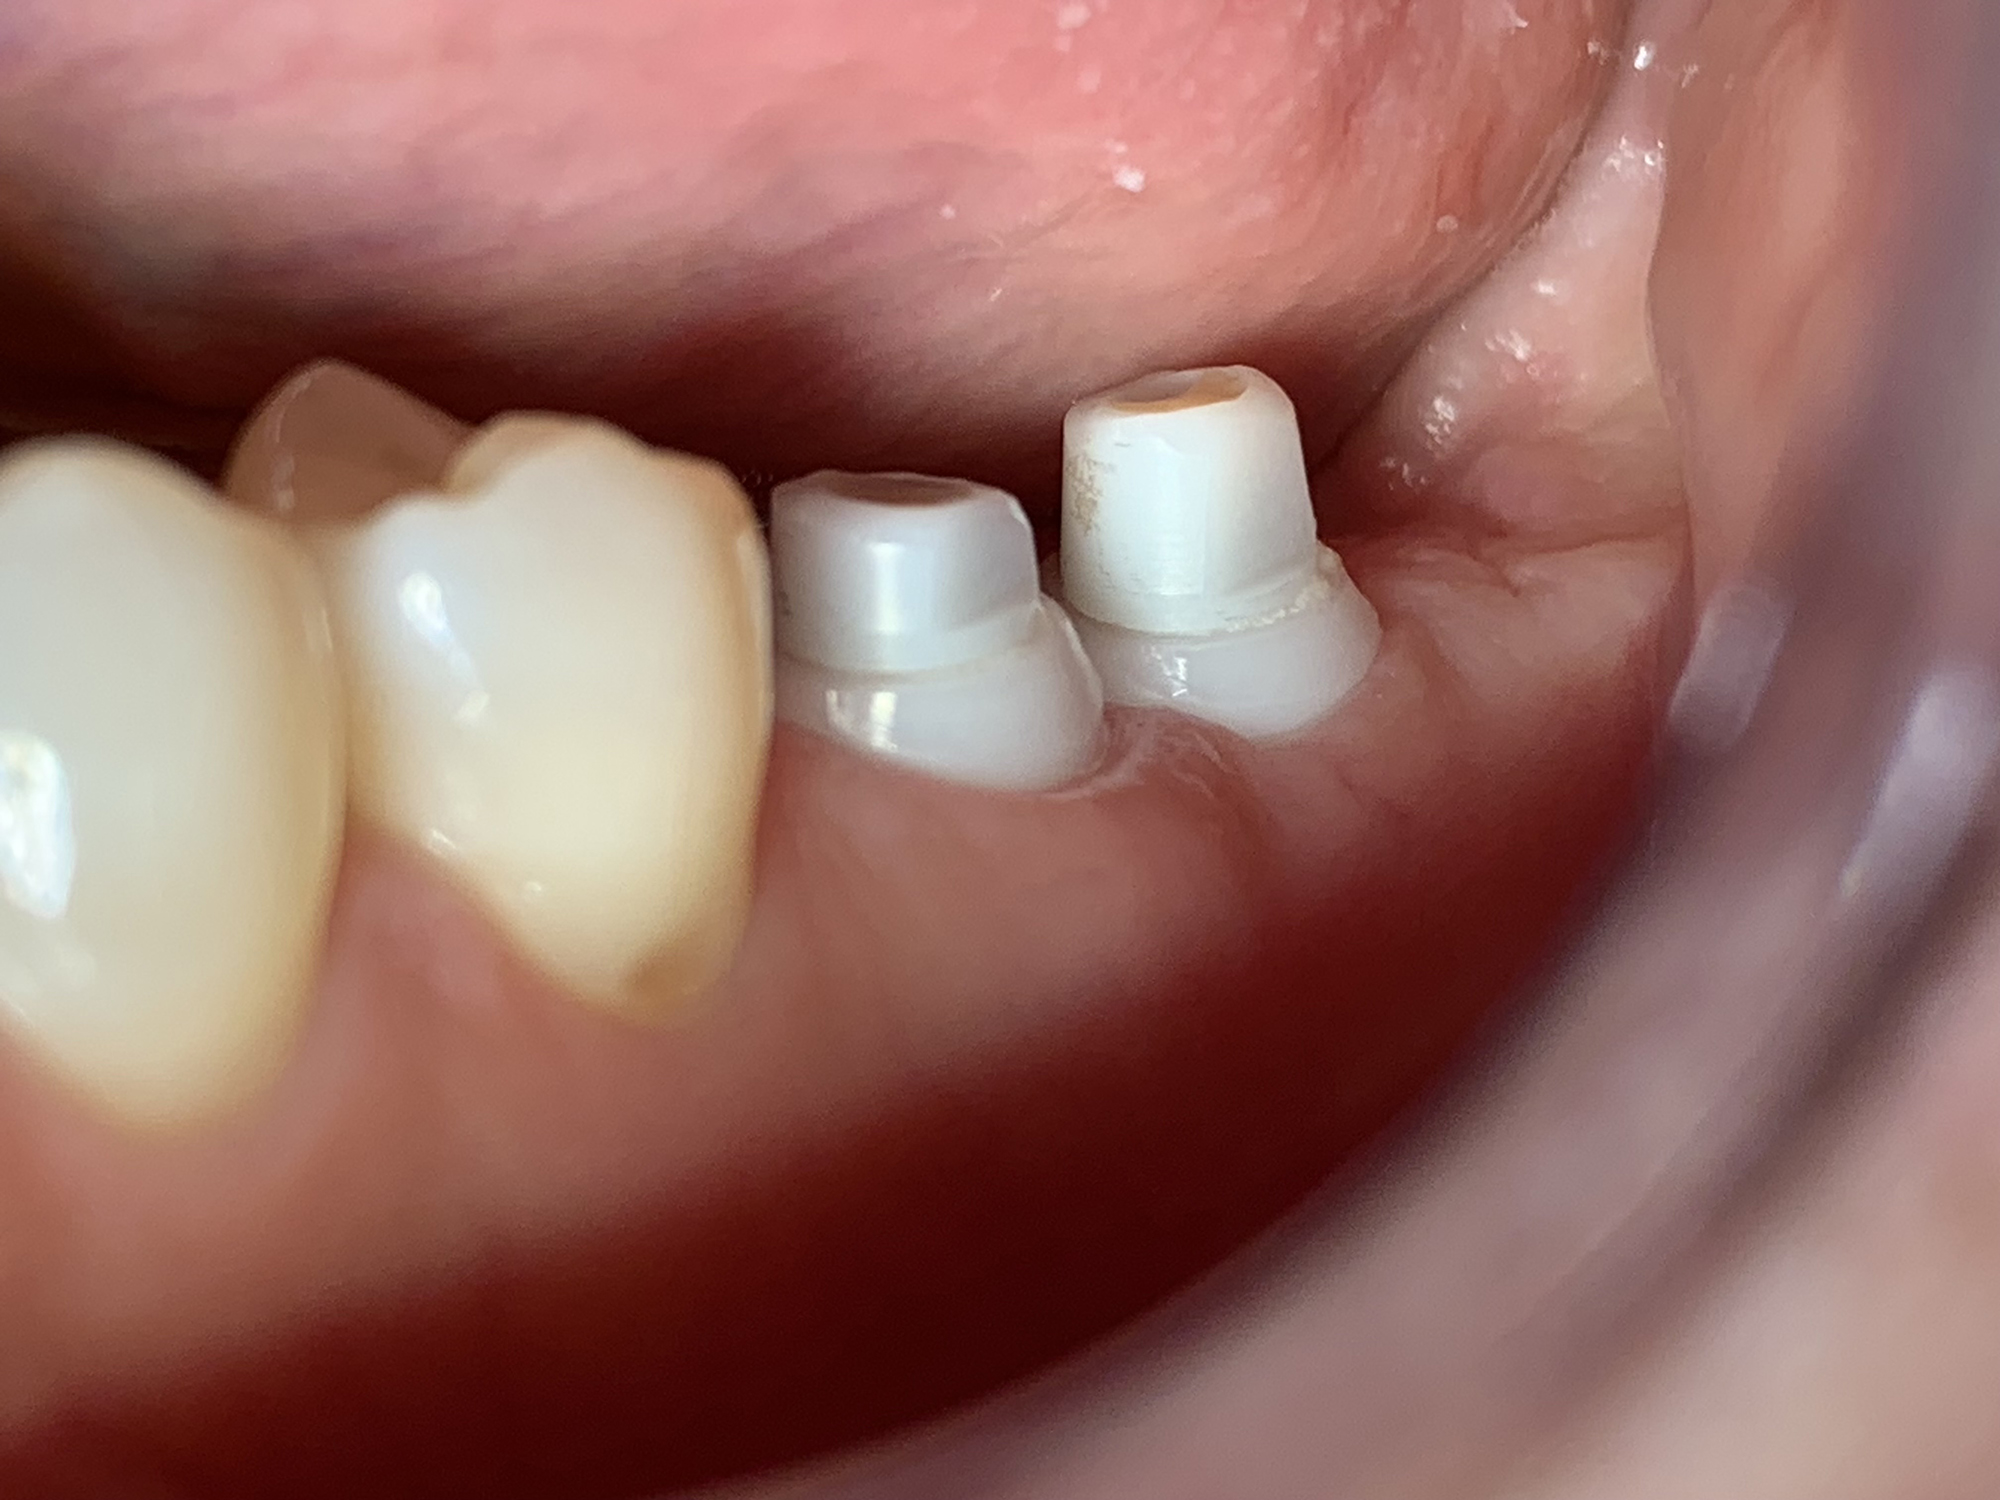

Keramikimplantate

Wir setzen auf hochwertige Keramikimplantate von Swiss Dental Solutions. Diese sind metallfrei, ästhetisch, verträglich und lassen sich oft in nur einer Sitzung einsetzen – für ein natürlich schönes Lächeln.

Keramikimplantat freigestellt

Vorteile Keramik Implantate

• Weiß

• metallfrei

• immunologisch neutral

• biokompatibel

• hochästhetisch

• keine Periimplantitis

• keine freien Elektronen an der Oberfläche – keine Reaktion mit Gewebe

• kein Störfeldcharakter

• kurze Behandlungsdauer